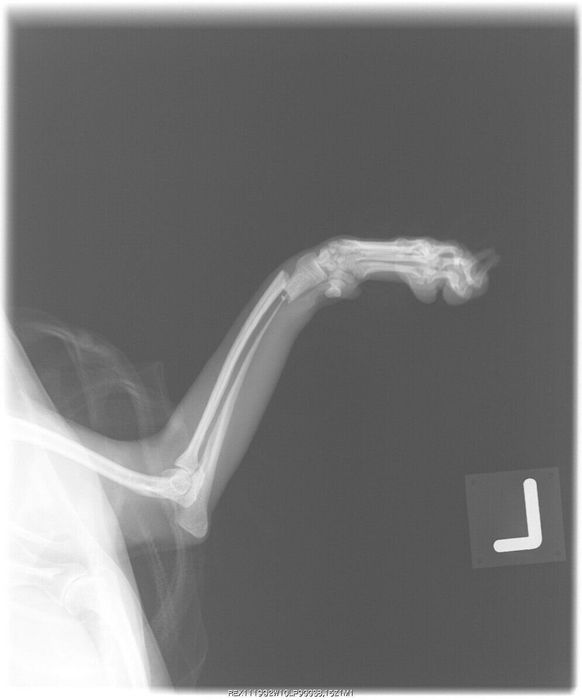

左足の膝蓋骨を脱臼している、生後9カ月のチワワのエックス線写真

健康な犬の膝関節は、「ひざのお皿」と呼ばれる膝蓋骨が、くぼみにはまった状態になっています。膝蓋骨脱臼は、この膝蓋骨がなんらかの原因によってくぼみからずれてしまう病気です。